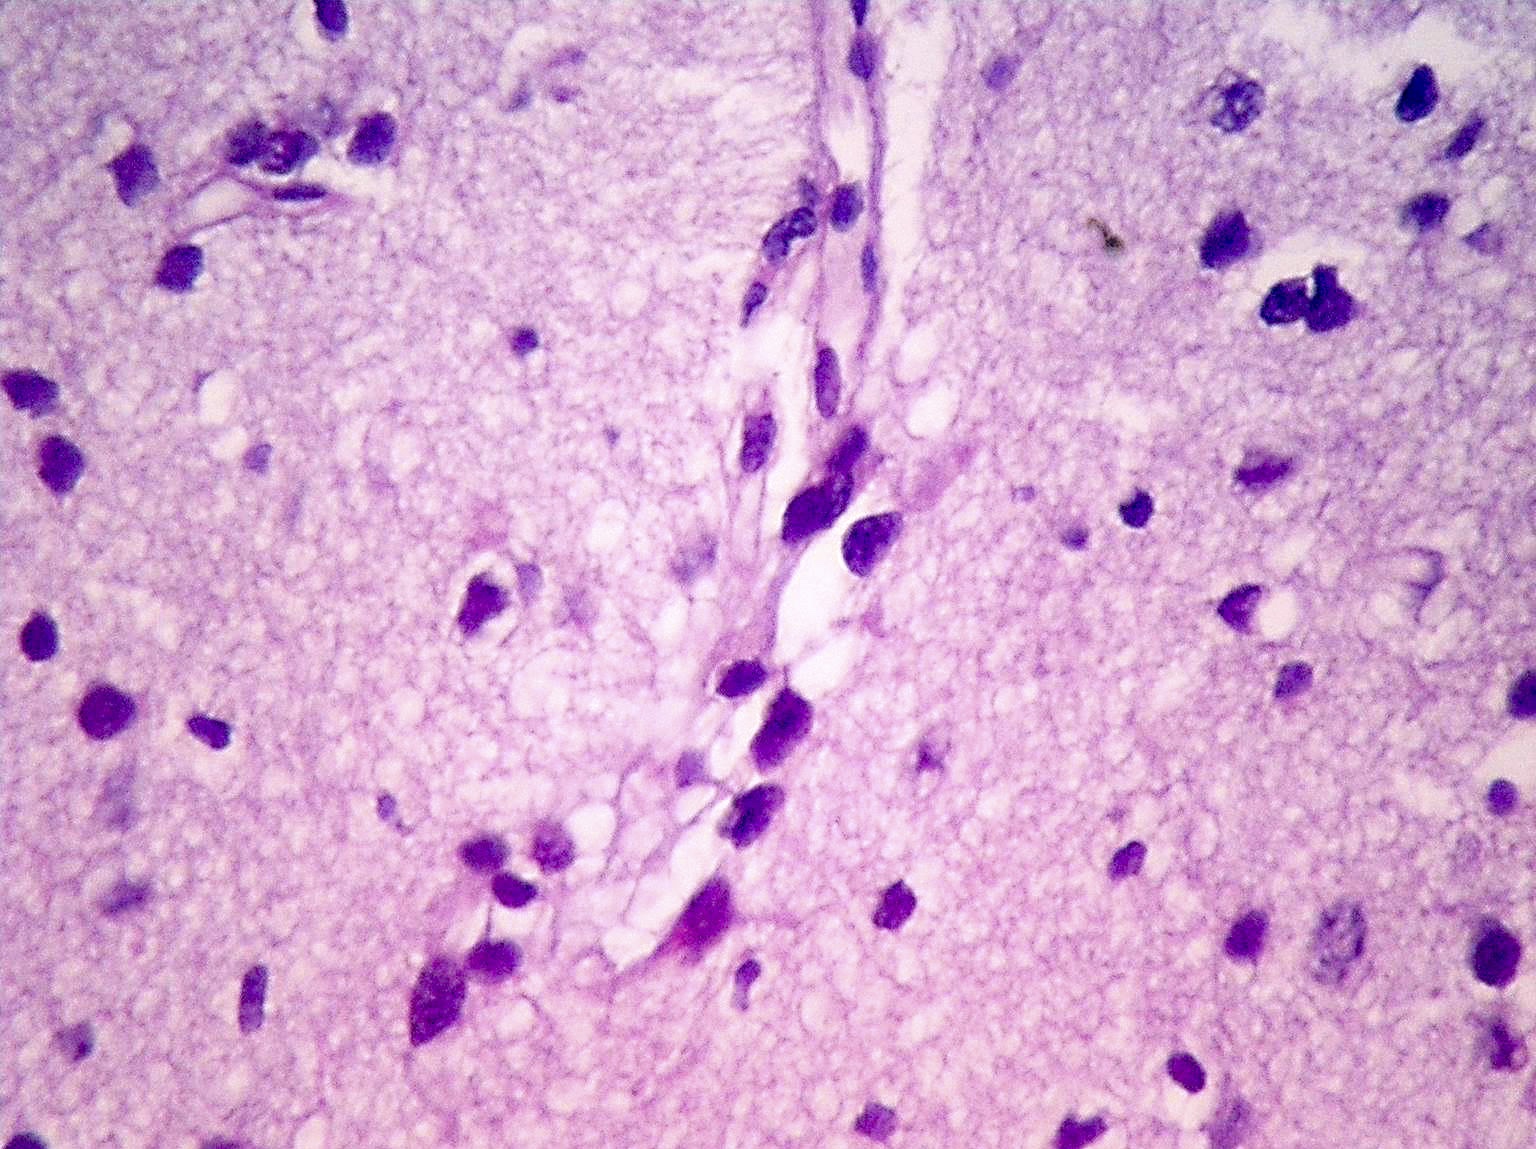

Microscopic (histologic) description

- Diffusely infiltrating tumor cells with oval to elongated astrocytic nuclei and varying appearance of tumor cytoplasm and fibrillar glial processes (Acta Neuropathol 2015;129:789)

- At the periphery, tumor cells may infiltrate in a diffuse single cell pattern, often with entrapped neurons and axons

- Cellular morphology is variable, even within a single tumor

- Commonly there is a mix of cells with elongated nuclei and fine fibrillar processes, cells with eccentric nuclei and glassy eosinophilic cytoplasm (gemistocytes), larger pleomorphic cells and small cells with scant cytoplasm

- May show oligodendroglioma-like areas

- Myxoid background and microcyst formation may be present

- Variable mitotic activity, cellularity and nuclear atypia depending on CNS WHO grade

- In small biopsy specimens, the presence of 1 mitosis may be sufficient for a CNS WHO grade 3 diagnosis, while the presence of a few mitotic figures in a large resection would not be sufficient for grade 3 designation (Acta Neuropathol 2020;139:603)

- Presence of necrosis or microvascular proliferation would be consistent with a CNS WHO grade 4 designation

Microscopic (histologic) images

Contributed by Eman Abdelzaher, M.D., Ph.D., John DeWitt, M.D., Ph.D. and Meaghan Morris, M.D., Ph.D.